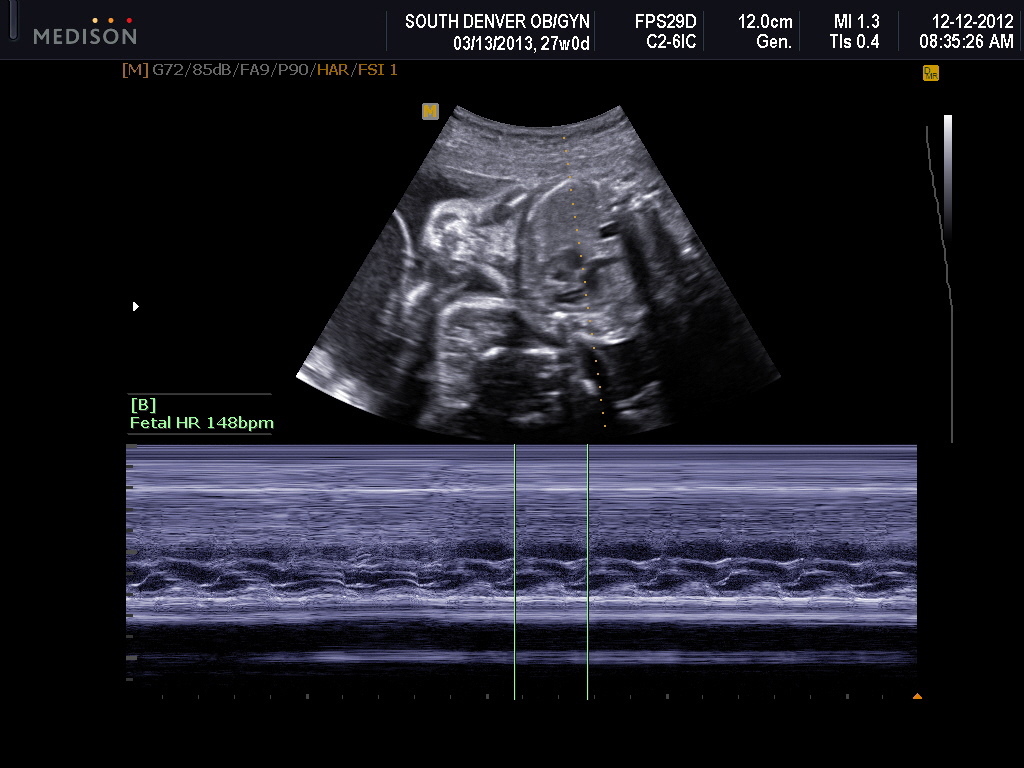

As of today I am 27 weeks and 4 days.  I went for a growth ultrasound on Wednesday and it was so nice to check on my little boys!!  Baby A measured approx 2 weeks ahead at 2lbs 15oz (83rd percentile) and Baby B measured just a couple days ahead at 2lbs 6oz (53rd percentile.)  They are some big boys!!

They like twins to be within 25% of each other weight wise and the little boys are currently about 20% different according to the ultrasound measurements.  The measurements could be off, but they might not be either.  The doctor said that we will be watching them closely from here on out just to make sure the discrepancy doesn't get any larger... although I'm not really sure what we would do about it anyways.  He did say though that usually the problem is that one baby is a lot smaller than the other (like in the lower percentiles) but in our case, baby A is just a very big boy and baby B is doing just fine.

As of right now, A is head down and B is transverse with his head on my right and pretty much laying sideways on the top of my belly.  The boys butts are pretty much on top of each other! So, I guess we will see if they decide to flip or move positions... which they probably will.  I haven't really made any decision yet on which type of delivery it will be... just depends on their positions and what the doctor recommends when the time comes I suppose.   Oh!  Can't forget... Cervix is measuring GREAT.  4.2cm and 3.8 with compression.  No funneling or opening up in any way!

No pictures of Baby B's face :(  He was looking towards my back and wouldn't turn!! But look at all of that hair they already have!!